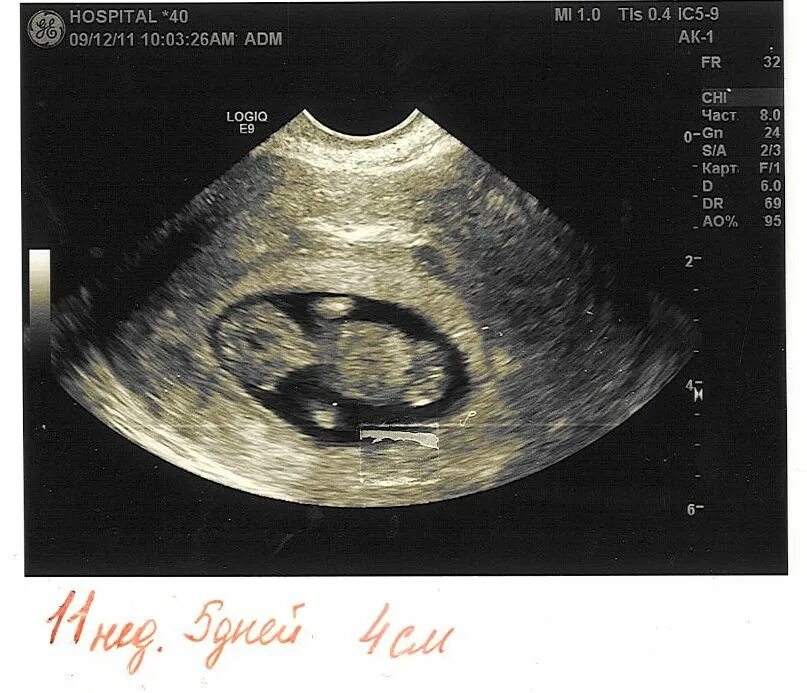

11 недель и 5 дней